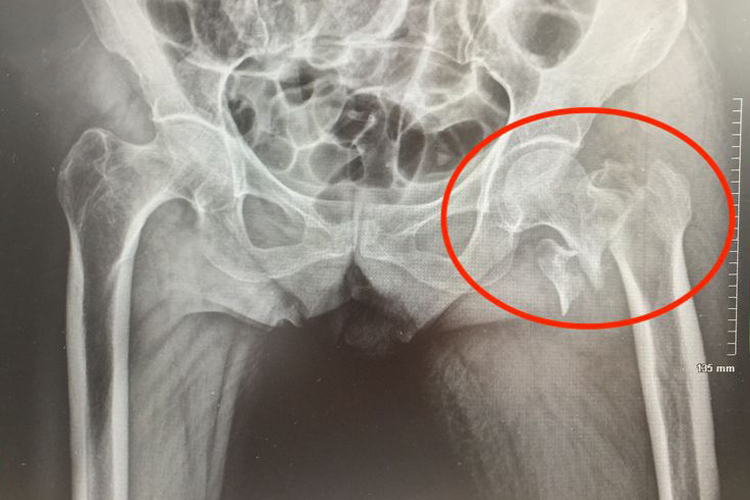

髋关节后脱位可表现为髋关节处于屈曲、内收、内旋弹性固定位,下肢有短缩畸形,大粗隆向后上脱位可达Nelaton线之上,患侧臀部可以触及股骨头。患者往往自觉髋部疼痛明显,患肢不能正常活动。

股骨颈骨折主要表现为伤侧下肢呈45°-60°的外旋畸形,患肢缩短,Bryant三角底边缩短,股骨大粗隆顶端在Nelaton线之上。还会伴有患髋压痛、轴向叩击痛,下肢不能活动,行走困难等症状。